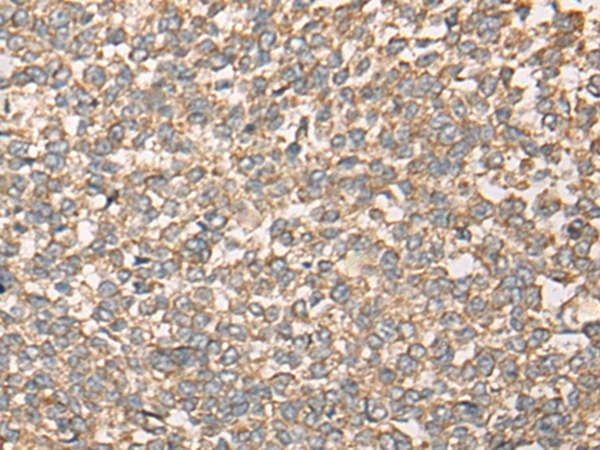

分类: 科研抗体货号: P09403别名: DVC1; PRO4323; spartan; C1orf124应用: IHC反应种属: Human, Mouse, Rat